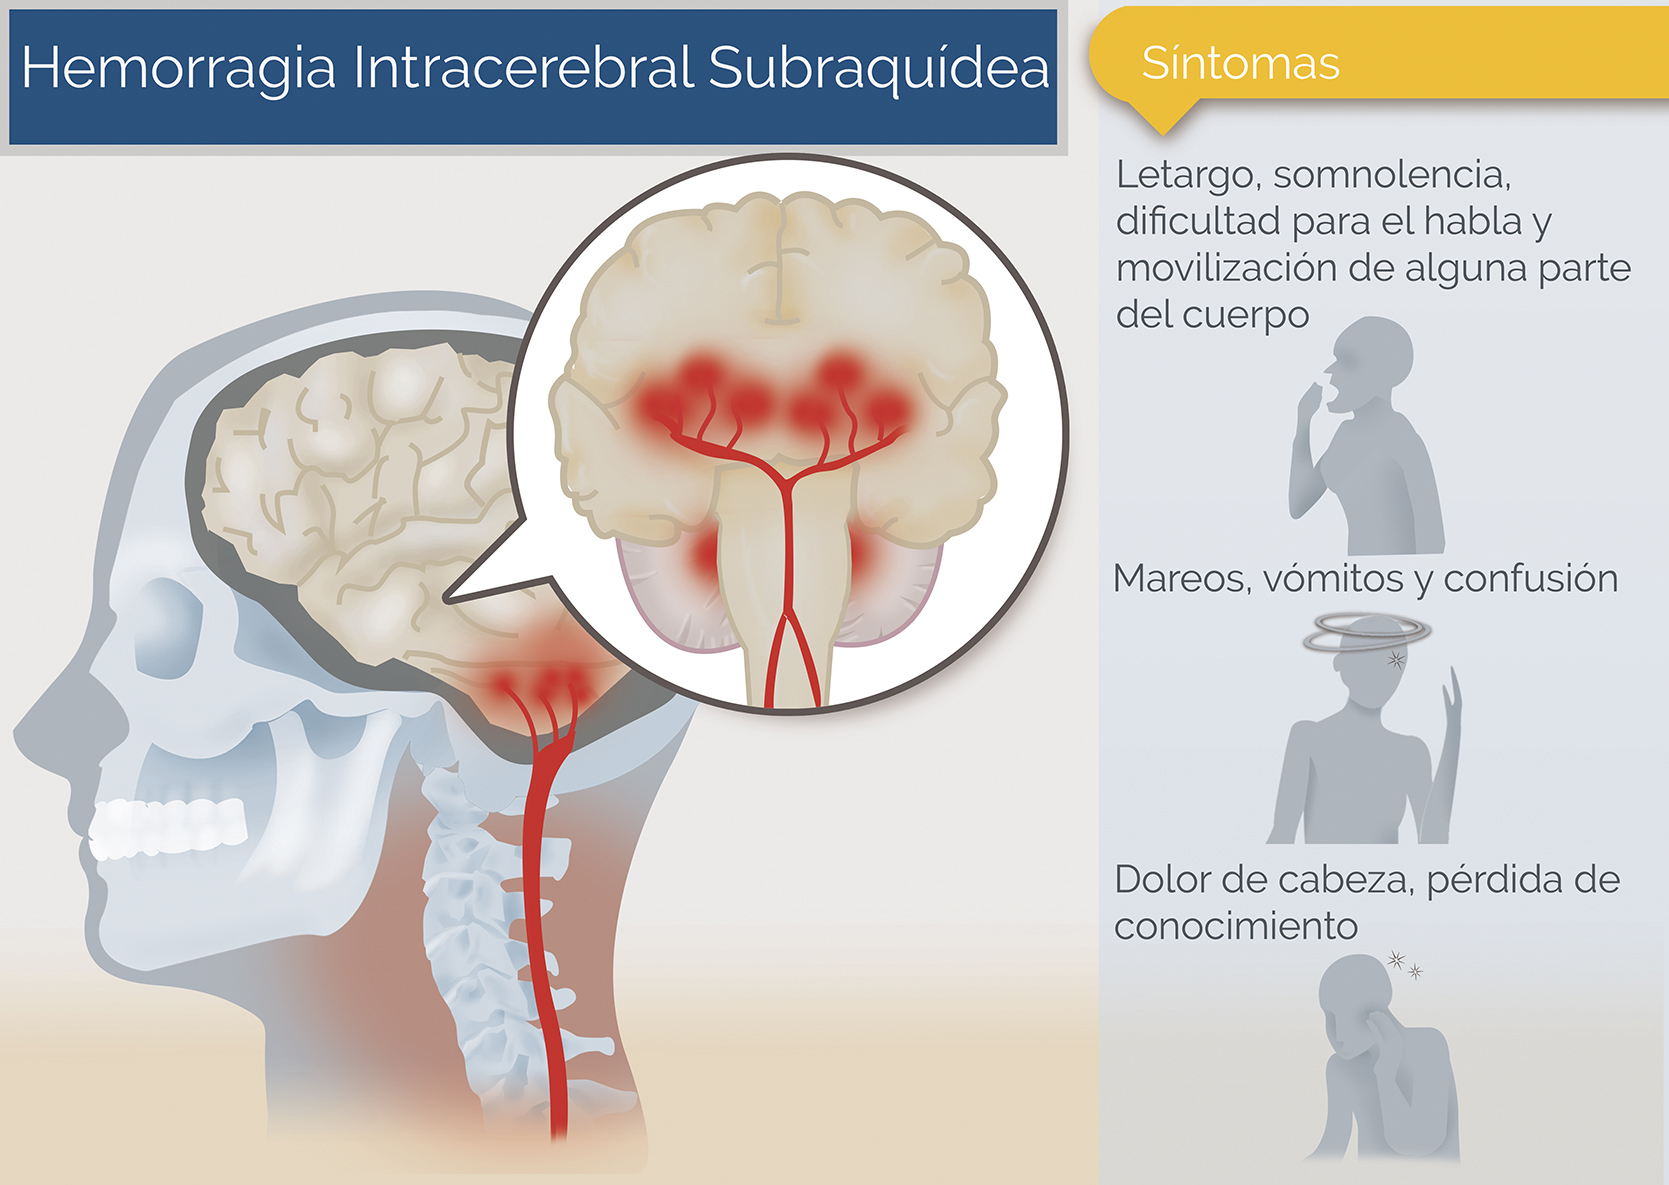

Hemorragia Intracerebral subraquídea Neurocirugía de la Torre

hemorragia cerebral Puede deberse a un trauma cerebral. The following 2 files are in this category, out of 2 total. Media in category intracerebral hemorrhage. La causa suele ser la hipertensión. Puede ser externo o dentro del cuerpo. Como ya se ha mencionado, suele estar relacionada con la hipertensión. Un hematoma intracraneal es una acumulación de sangre dentro del cráneo. En general, se distinguen entre hemorragias profundas (incluyendo aquellas que afectan a núcleos grises profundos de los hemisferios cerebrales), hemorragias.